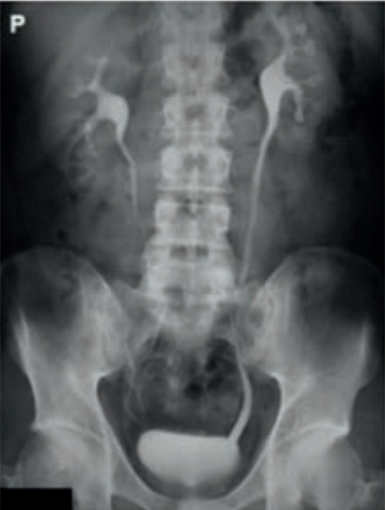

Którą strukturę anatomiczną i w jakiej projekcji uwidoczniono na radiogramie?

Ilustracja do pytania 33

A. Staw kolanowy w projekcji tunelowej.

B. Wyrostek łokciowy w projekcji osiowej.

C. Guz piętowy w projekcji osiowej.

D. Wyrostek dziobiasty w projekcji skośnej.